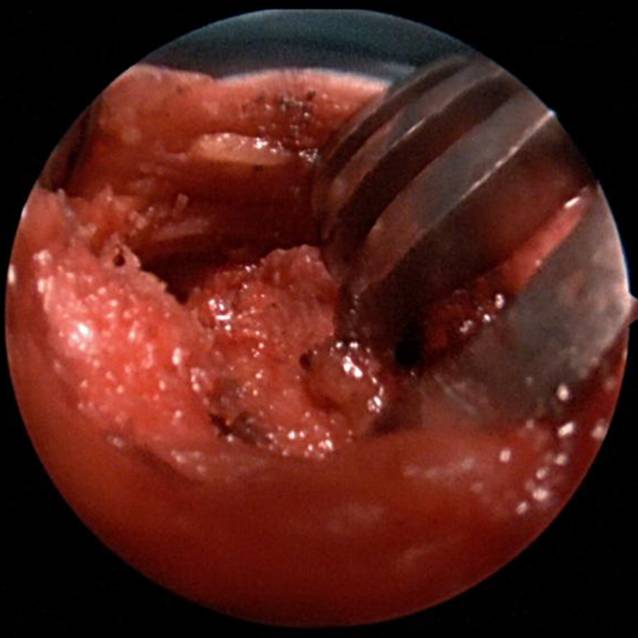

Abb. 3

Arthroskopie Schulter links: beginnende posttraumatische Omarthrose und Knorpelfragmente

Intraoperativ stellt sich eine ausgeprägte Synovialitis mit serösem Erguss und deutlichen Verklebungen dar. Es erfolgte eine Synovektomie und Bursektomie der Bursa subcoracoidea sowie die Entfernung multipler Knorpelfragmente (Abb. 3). Nach weiterer Präparation des Korakoids und des subkorakoidalen Raums war die Bergung des frei florierenden inferioren DogBone-Buttons ventral der Subskapularissehne möglich (Abb. 4). Anschließend konnten die Fäden und der superiore DogBone-Button mini-open dargestellt und ebenfalls geborgen werden (Abb. 5).